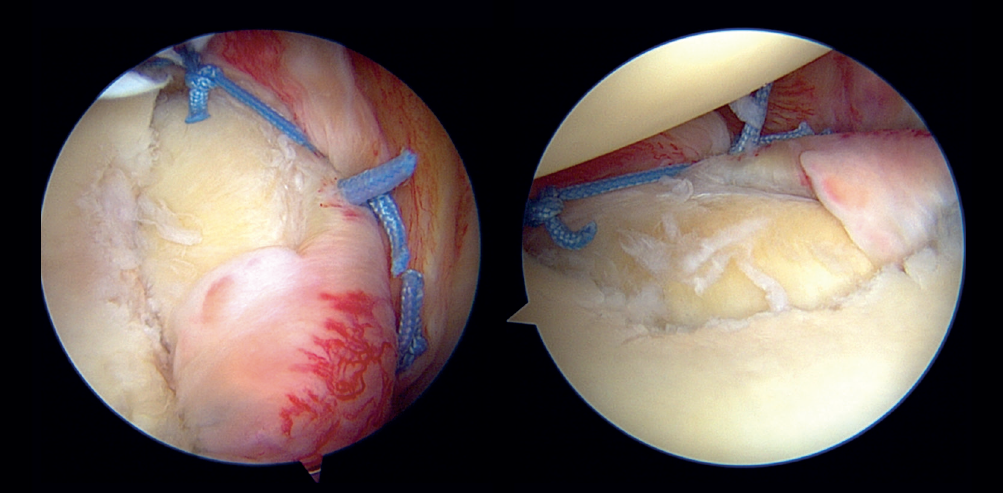

In the modified double-row/double pulley technique, and in addition to the measures commented above, an anchoring was added between the first implant and the second, at the height of half of the fractured bone fragment but in a position medial with respect to the chondral margin of the glenoid cavity (Figure 5). In this case, both the extremities crossed through the capsule at the level of half of the fragment and anterior to the latter at different points, followed by knotting and maintaining reduction of the bone fragment (Figure 6). One of the extremities of the suture knot made was tied to one of the extremities of the lower anchoring, while the other was tied to one of the extremities of the upper anchoring, thereby completing the repair procedure (Figure 7).